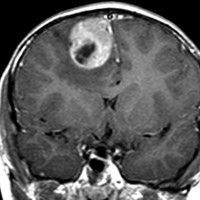

典型的な画像(未分化胎児性腫瘍の組織像を持つもの)

頭痛と嘔吐でみつかった年長児10歳のPNETです。脳外科の先生に上手に手術で全摘出していただいて,すぐに脳脊髄照射25.2グレイ14分割と局所追加照射30グレイ15分割の治療を受けました。その後に相談に来られたので,テモゾロマイド化学療法を24コース追加しました。

腫瘍は消失して元気に学校へ通えています。治療後IQは108あるのですが,右の前頭葉の上前頭回という所に発生したのが幸いであったかもしれません。この場所は確実に摘出できるからです。